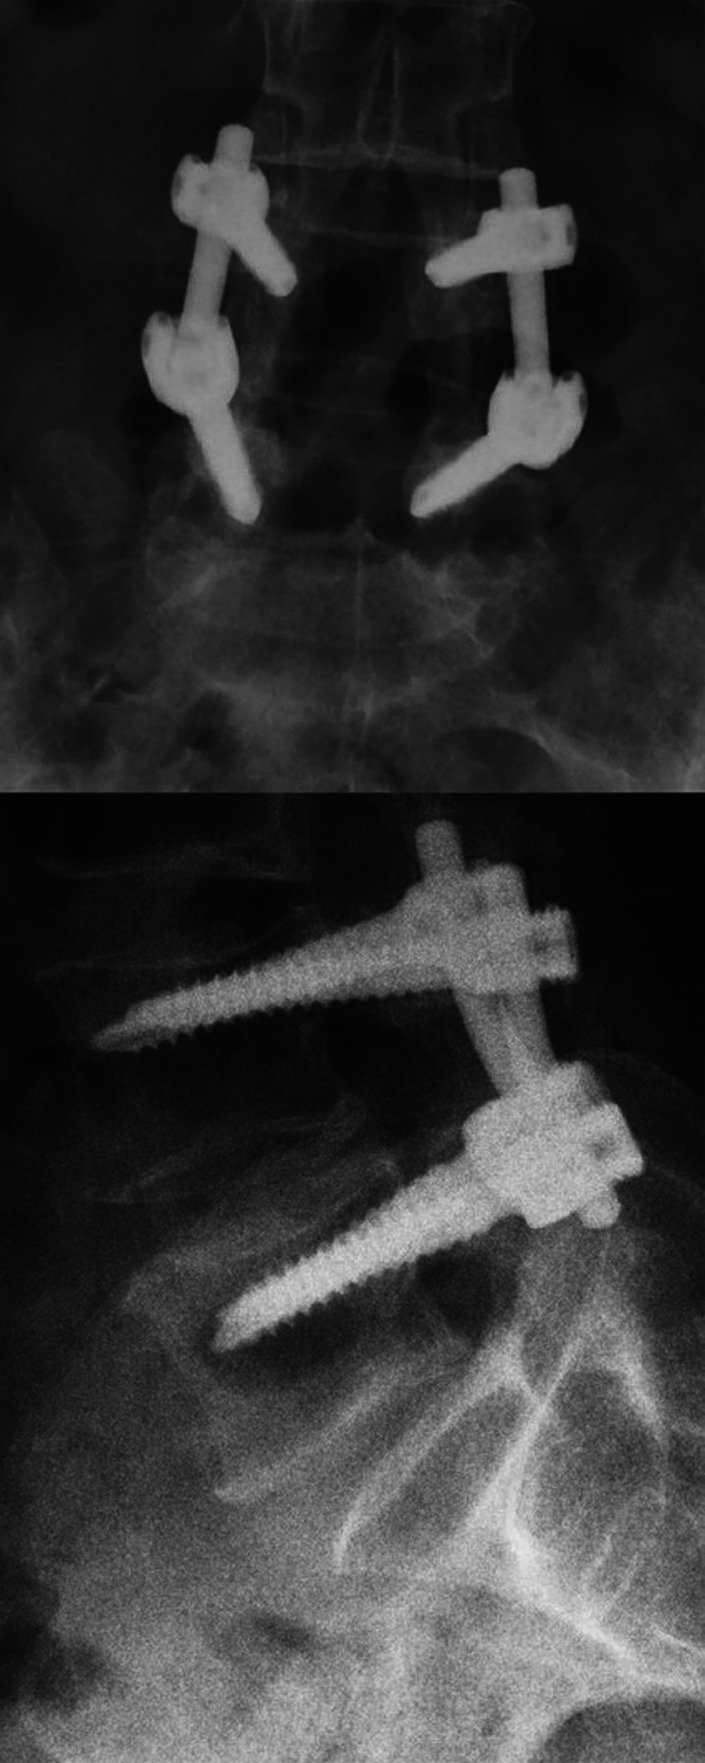

Methods: Sixteen patients with mono-segmental disc degeneration (L4-L5 or L5-S1) who underwent posterior lumbar spine fixation with intervertebral distraction of 2 consecutive vertebrae using monoaxial transpedicular screws and lyophilized allograft to achieve segmental fusion, and who had a follow-up period of at least 2 years, were included in this study. The first lumbar disc was used as the control group. The dGEMRIC studies in degenerative and control discs, visual analogue scale (VAS), Oswestry disability index (ODI), lumbar lordosis, and disc thickness were reviewed before and after surgery.

Results: Visual analogue scale and ODI showed significant improvements (P=.003, P=.0004, respectively). The thickness of the operated discs was increased by an average of 2.41 mm (P=.0004) while maintaining lumbar lordosis (P=.35). In pre- and post-surgery dGEMRIC studies, the operated discs showed a significant di!erence (P=.0013), while the control groups remained approximately unchanged (P=.87).